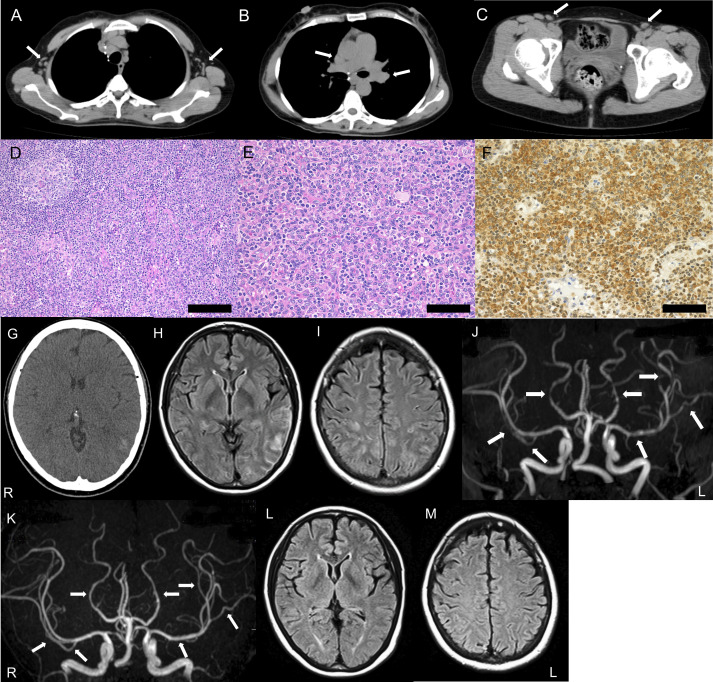

Case presentation: We report the case of a 58-year-old female patient with at least a 3-year history of iMCD, who experienced acute thunderclap headaches due to reversible cerebral vasoconstriction syndrome (RCVS). RCVS occurred 3 months after initiating treatment with tocilizumab, a humanised anti-IL-6 receptor monoclonal antibody, and was accompanied by focal cortical subarachnoid haemorrhage (SAH). Elevated IL-6 levels were found in both serum and cerebrospinal fluid. MR angiography revealed multiple diffuse stenotic lesions in the bilateral middle and posterior cerebral arteries, which, along with bilateral cerebral oedema, resolved within 3 months. The diffuse nature of the cerebral vasospasm and the presence of bilateral brain oedema suggested that cerebral vasospasm was due to RCVS rather than SAH.